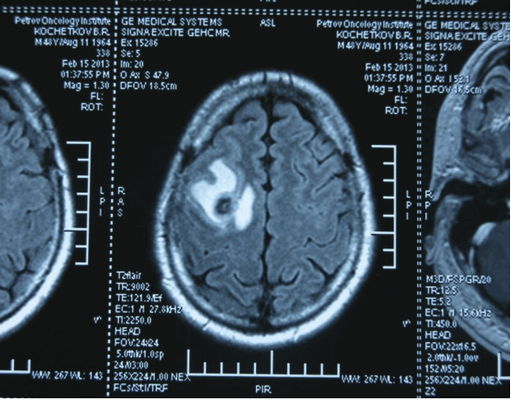

Головной мозг

Герминогенные новообразования в данной области - это примерно 2-4% от всех внутричерепных (интракраниальных). Патология в 75% случаев диагностируется у мальчиков, за исключением турецкого седла, где новообразования в основном локализуются у девочек.

Герминомы формируют инфильтрирующие опухоли больших размеров, часто являющиеся источниками субарахноидальных (между мягкой и паутинной оболочками мозга) и вентрикулярных (желудочковых) метастаз.

Рисунок 7. - Герминома головного мозга.

- КТ (расшифровка: компьютерная томография), МРТ (расшифровка: магнитно-резонансная томография), ПЭТ-КТ (расшифровка: позитронно-эмиссионная томография, совмещенная с КТ). Эти обследования необходимы, чтобы рассмотреть структуры организма послойно и визуализировать опухоль. Они показывают, как сильно распространен патологический опухолевый процесс на находящиеся рядом ткани и органы, есть ли поражение костей. КТ - это самый чувствительный метод для обнаружения метастазов в легких. Проведение МРТ и КТ головного мозга необходимо, чтобы обнаружить и визуализировать герминогенные новообразования эпифиза.

Рисунок 9. - метастаз в головной мозг при герминогенной опухоли.

Лечение

Герминогенные опухоли центральной нервной системы (головного мозга) имеют следующие клинические проявления: головная боль, расстройство движений глазных яблок, тошнота, рвота и развитие судорог.

Также выполняют МРТ головного мозга, чтобы выявить наличие метастазов в нем.